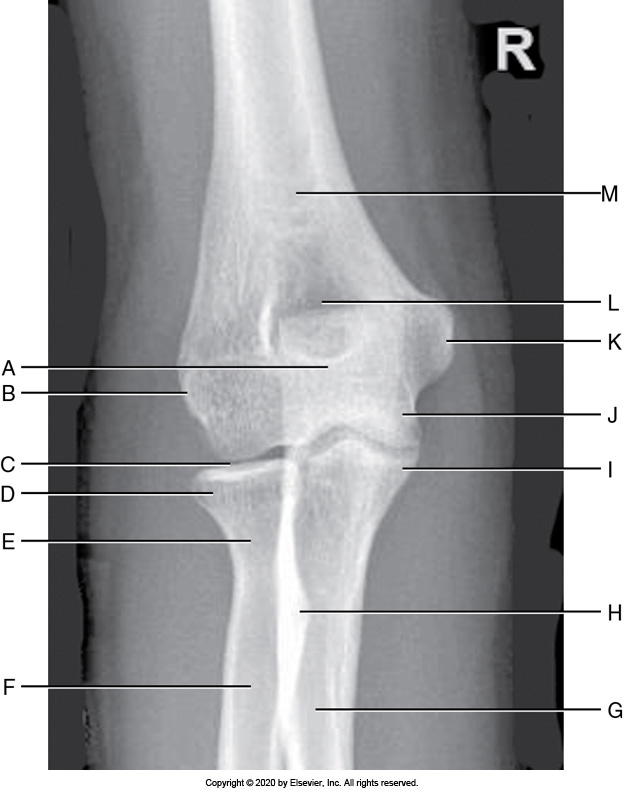

Identify the labeled "D" anatomy in the image below:

Medial epicondyle